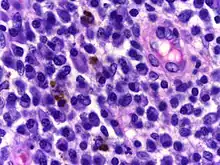

![]() | Plasma cells | Plasma cell showing eccentrically placed round nucleus with cart wheel like chromatin. | Category: Plasma cells | Plasma cell |